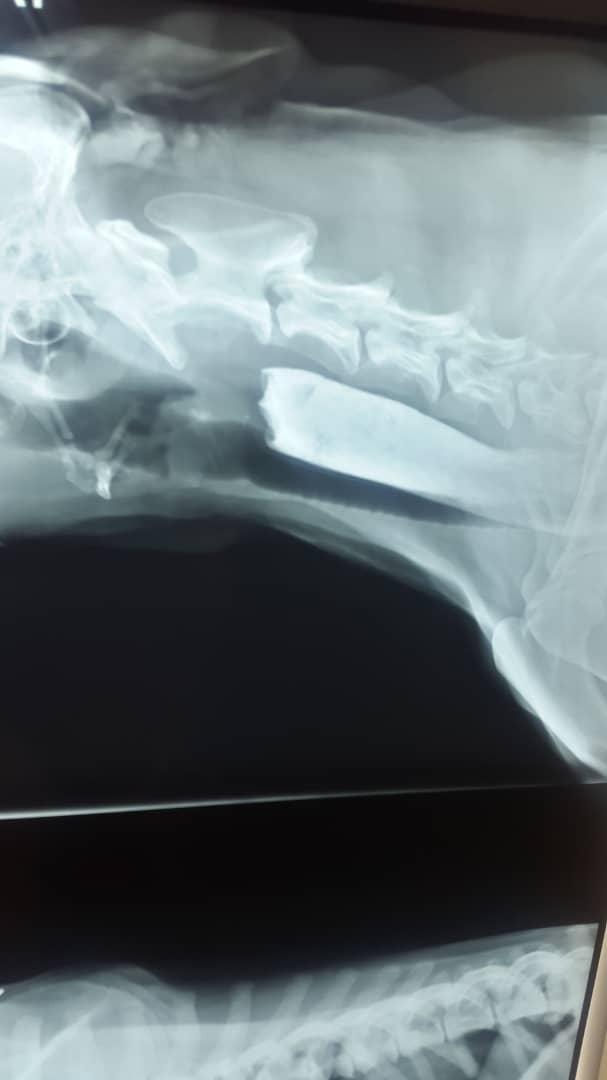

I have a 10 yo AKC registered labrador who currently lives in overseas. He has developed severe dysphagia, barrium swallow showed obstruction and CT scan showed large lung tumor. His Vet in overseas says nothing can be done for him. But I want a second opinion from a vet in US please look at the CT and let me know. I only can send 3 images here. But I have more. Thanks

The problem is that you can possibly try to remove the tumors with surgery. However, your dog is an old dog and the anesthetic risk in a dog with a large lung tumor at this age is great and it is likely that your dog will die during anesthesia. The obstruction can probably be removed, but again the anesthetic risk is great. Recuperation will also be extensive and there is a big chance that your dog's tumors will reoccur before he has even returned to wellbeing from the surgery, should he have survived it. I agree with the veterinarian who diagnosed him (considering what you have reported). You can get a second opinion from an oncologist overseas. They are no worse than the ones here in the US. I am sorry your dog is so ill.